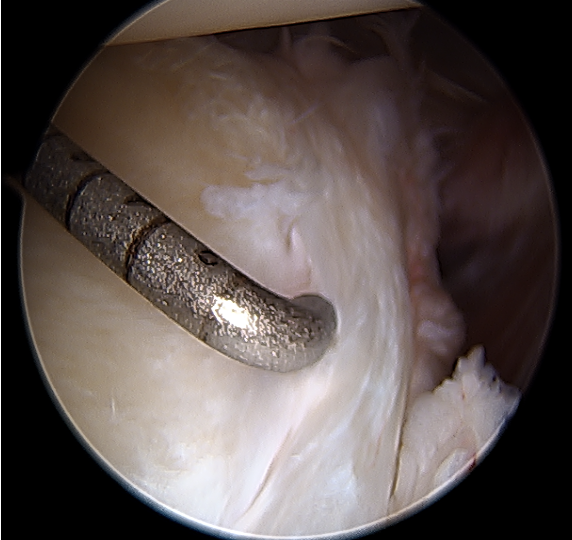

Arthroscopy

Capsule tear anteriorly, extending up into humeral insertion

Side to side repair of capsular tear

Intact anterior labrum with capsular tear, axillary nerve seen below capsular tear in axillary recess